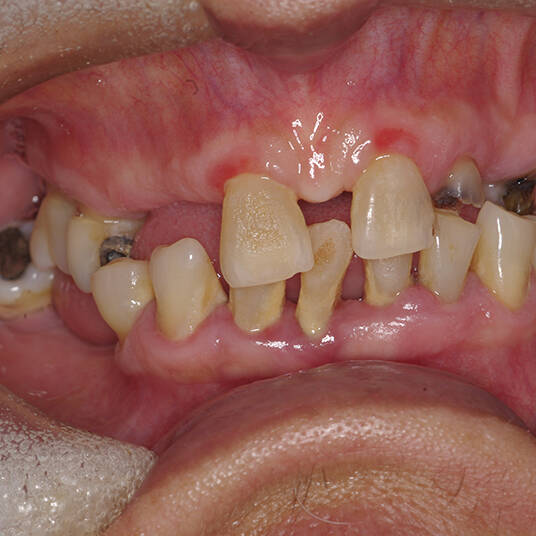

Embora seja uma solução moderna, nem todos os pacientes são candidatos ideais para a Carga Imediata. O sucesso do tratamento depende de fatores como:

- Quantidade e qualidade do osso disponível.

- Ausência de infecções ou doenças periodontais ativas.

- Condições gerais de saúde que favoreçam a cicatrização.

Por isso, uma avaliação personalizada com um especialista é essencial para determinar se a técnica é indicada para o seu caso.